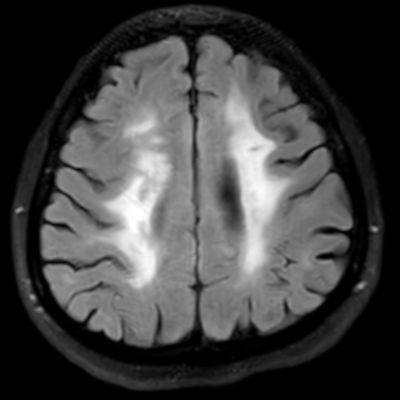

45 yaş, K

4 yıl önce akut sağ hemiparezi, konuşma bozukluğu ve dış merkezde serebellar iskemi tanısı ile ASA kullanımı öyküsü

Konuşma bozukluğu, yersiz gülme ve ağlama atakları, denge kaybı ve uyuşmaları devam ediyor

CADASIL